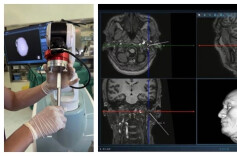

脑控听觉技术可精准实现“听你想听”